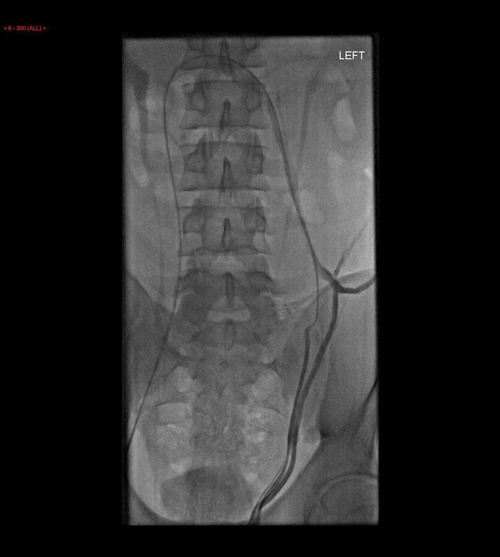

Figure 6: Static image showing the catheter in the left testicular

vein and contrast seen to outline the dilated vein.

Possible methods of treatment include sclerosing agents, metallic coils and detachable balloons. This is minimally invasive and has a faster recovery time compared with surgical repair and can be performed under local anaesthetic. The left spermatic vein is cannulated (Figure 6) and coils, or other material to be used, inserted and then the vein is reassessed to ensure the varicocele has been treated (Figure 7). Five to ten percent of varicoceles recur after embolisation and therefore it is recommended that patients undergo a routine ultrasound in approximately four weeks to ensure the varicocele has not returned.